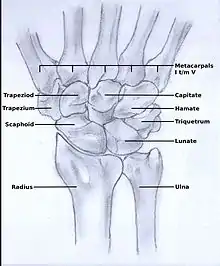

The Wrist Complex

The wrist complex is comprised of the radiocarpal and midcarpal joints, both of which are surrounded by a joint capsule lined with a synovial membrane and strengthened medially by the ulnar collateral ligament and laterally by the radial collateral ligament [11]. The radiocarpal joint consists of the distal radius and the lunate and scaphoid. The remaining carpal bones, articulating with the proximal surfaces of the lunate scaphoid and triquetrum make up the midcarpal joint [11]. Blood supply to the complex is via branches of the dorsal and palmar arches with innervation via branches of the ulnar, medial and radial nerves [11]. There are nine muscles located in the forearm the tendons of which cross the wrist and are inserted in the hand that work together to produce the various movements possible at the wrist. Extension of the wrist is produced by the extensor carpi radialis longus, radialis brevis and extensor carpi ulnaris [12][11]. Flexion is possible due to the flexor carpi ulnaris and flexor carpi radialis muscles with some assistance from the finger and thumb flexors and palmaris longus [12][11]. Adduction of the wrist occurs when extensor carpi ulnaris and flexor carpi ulnaris work together whilst abduction requires the combination of flexor carpi radialis, extensor carpi radialis brevis and longus along with abductor pollicis longus [11]. With its combination of complex articular surfaces, muscular, vascular and nerve supplies, any injury or inflammation at this joint complex can affect movements in other joints both proximally and distally. The importance of preserving the functionality of these joints should not be underestimated. In order to function optimally, joints of the upper limb need to be able to move smoothly and friction free, their small cartilaginous articular surfaces unhindered by scars or adhesions that may restrict their movement[4]. In particular, the functioning of the hand may be reduced significantly if there is anatomic re-arrangement of tissues or an alteration to its physical characteristics[4]. Unfortunately, due to the very nature of the disease, RA frequently alters the alignment and positioning of affected joints, particularly in its advanced stages[1][2].